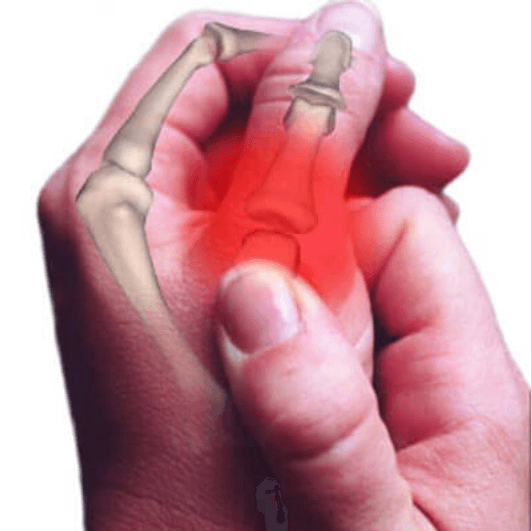

Αυτός ο ήχος που ακούμε όταν κάνουμε κρακ στα δάχτυλα, τους καρπούς μας, τους αστραγάλους μας ή οποιοδήποτε άλλο σημείο του σώματός μας προέρχεται από το σπάσιμο των φυσαλίδων που βρίσκονται στην υγρή επίστρωση των συνδέσμων μας. Είναι καλό να θυμάστε ότι οι σύνδεσμοί μας αποτελούν το σημείο επαφής που συγκεντρώνονται τα οστά μας και καλύπτονται από ένα παχύρρευστο “αρθρικό” υγρό. Όταν για παράδειγμα ο σύνδεσμος ενός δαχτύλου σπάει, τεντώνεται ή λυγίζει, διαχωρίζεται.

Η μεμβράνη που περιβάλλει τον σύνδεσμο απλώνεται και διευρύνεται με αποτέλεσμα να μειώνει την πίεση που δέχεται ο σύνδεσμος. Όταν συμβαίνει αυτό, τα αέρια που βρίσκονται μέσα στο αρθρικό υγρό σχηματίζουν φυσαλίδες οι οποίες “εκρήγνυνται” κάνοντας αυτόν τον χαρακτηριστικό ήχο σπασίματος.

Κατά τη διάρκεια αυτής της μελέτης ανακαλύφθηκε ότι τα δάχτυλα παρουσίαζαν σημάδια βλάβης, όπως τραυματισμούς των μαλακών ιστών και μειωμένη δύναμη της λαβής. Αυτό απ’ ότι φαίνεται σχετίζεται με το γρήγορο και επαναλαμβανόμενο τέντωμα και τη συστολή των συνδέσμων που στηρίζουν τις αρθρώσεις.

Συχνά θέλουμε να ανακουφιστούμε από τον πόνο ή τις συσπάσεις και κάνουμε αυτήν την κίνηση, αλλά επίσης θα πρέπει να γνωρίζουμε ότι για τις αρθρώσεις μας αυτή η κίνηση θεωρείται απότομη, σκληρή και αφύσικη. Και σε αντίθεση με τη γνώμη του κοινού, δεν απαλύνει την μυϊκή ένταση αλλά μάλλον έχει ως αποτέλεσμα την απώλεια μεγαλύτερης ποσότητας αρθρικού υγρού, το φυσικό λιπαντικό που προλαμβάνει την τριβή μεταξύ των οστών. Αυτό όχι μόνο μπορεί να οδηγήσει στη φθορά των συνδέσμων αλλά ακόμη πιο πιθανό είναι να υποφέρετε από κάταγμα ή σπάσιμο των οστών. Άλλες συνέπειες είναι η δυσκαμψία, η παραμόρφωση της τραυματισμένης περιοχής και έντονος πόνος που περνά μόνο με την ξεκούραση.